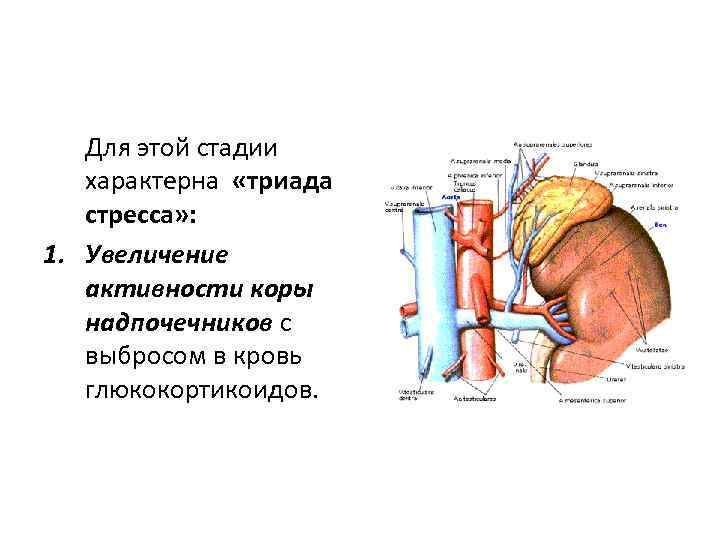

Для этой стадии характерна «триада стресса» : 1. Увеличение активности коры надпочечников с выбросом в кровь глюкокортикоидов.

Для этой стадии характерна «триада стресса» : 1. Увеличение активности коры надпочечников с выбросом в кровь глюкокортикоидов.

2. Уменьшение размеров тимуса, лимфатических узлов и селезенки под действием глюкокортикоидов.

2. Уменьшение размеров тимуса, лимфатических узлов и селезенки под действием глюкокортикоидов.

3. Изъязвление слизистой оболочки желудочнокишечного тракта.

3. Изъязвление слизистой оболочки желудочнокишечного тракта.